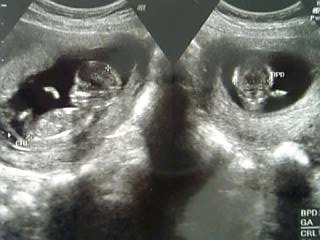

14weeks3days

14weeks1days

13weeks3days

13weeks1days

13weeks0days